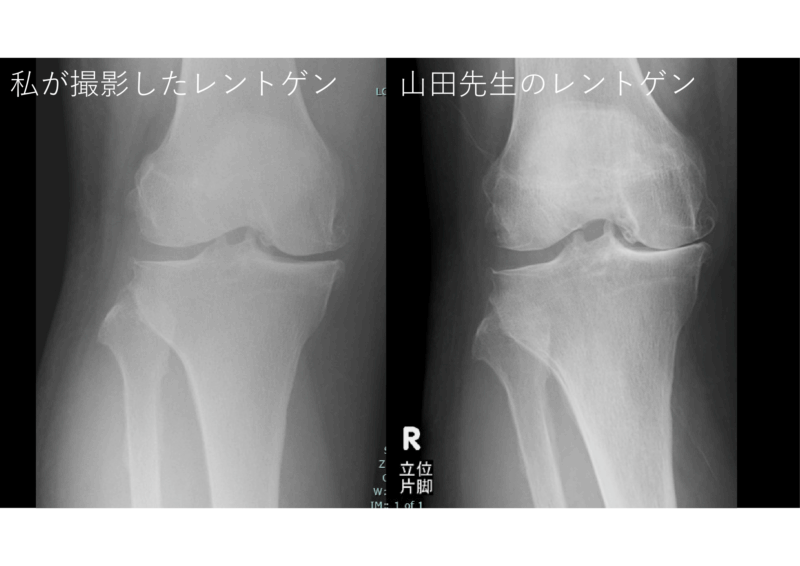

患者さんは3年近く診させていただいている70代テニスガールです。少し身体大きめ。右ひざ痛に対して私が以前撮影したレントゲン、内側の軟骨は結構残っていて、それほど悪くなさそう。その後、痛みが強く、MRIで骨傷を見つけました。でも結局、手術って痛みと軟骨の減り方というか、変形性膝関節症のグレードで決まるしなあ、と思っていたところで整形外科専門医の先生に相談しました。

優しく、色々と整形外科のことを教えてくれます。左は私が依頼した荷重かけずに撮影していた膝のレントゲン、整形外科専門医がオーダーすると右の図のように軟骨のすりヘリが明らかになる。これなら手術適応かもしれない。とても勉強になりました。